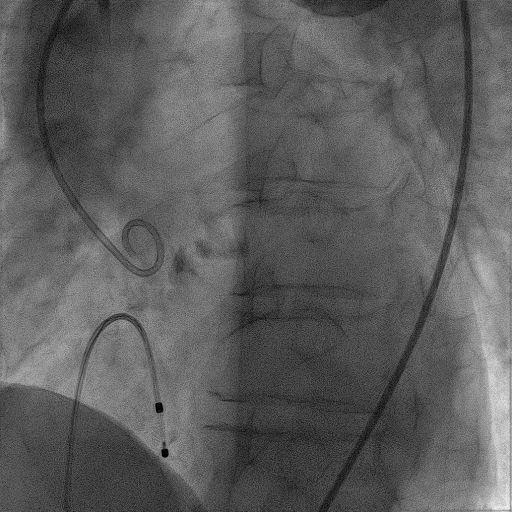

手术过程:

患者麻醉方式采取监护麻醉,建立静脉通路后,穿刺右肱动脉置入鞘管,穿刺右股动脉预置Proglide缝合器,置入动脉鞘管。右股静脉宜置入鞘管,经股静脉置入临时起搏器。经右股动脉行冠脉造影提示冠脉多处50%-60%狭窄。塑性后的加硬导丝送至左心室内,18mm球囊预扩张,主动脉根部造影提示右冠未见显影,右冠植入Chimney支架,同时释放TaurusElite® AV23主动脉瓣膜,造影示右冠血流通畅,瓣膜形态良好,结果满意。应用ProGlide缝合右股动脉穿刺部位并拔除临时起搏电极。术后患者即刻苏醒,安全返回普通病房。

主动脉根部造影

18mm球囊预扩张

23mm瓣膜精准定位

瓣膜+Chimney支架释放

瓣膜形态良好,结果满意